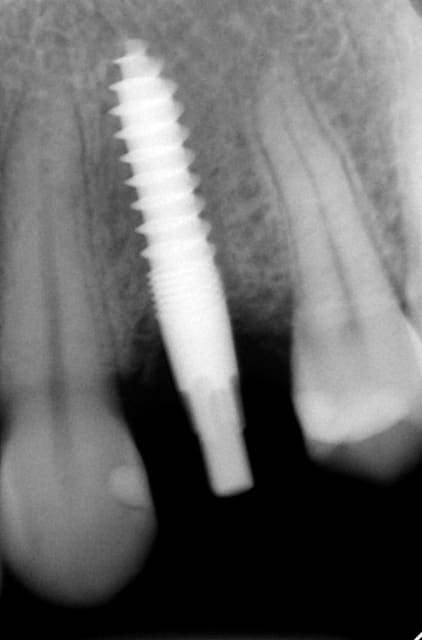

Donc l'idée est de réaliser un forage à minima en trans gingival avec un foret pyramidal. Pistez mes posts j'ai déjà mis des photos et radios en commentaire des deux sujet ouverts par le dr Nedjat.

Vous pouvez faire une radio foret en place, il faut verifier l'intégrité des parois osseuses à la sonde.

Clairement on sait comment va être placé l'implant, l'emmergeance prothétique, la relation aux adjacentes et antagoniste.